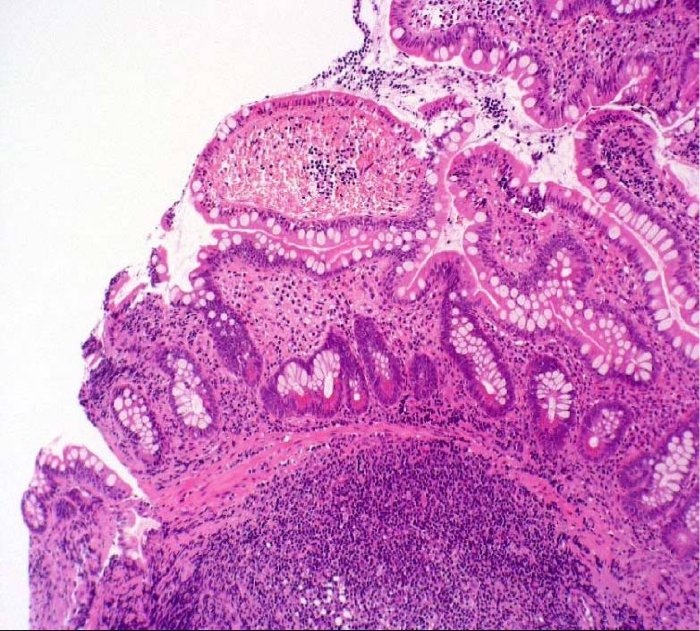

L'esame

dirimente per poter fare diagnosi di INL è la colonscopia che

consente da una parte di evidenziare i follicoli ipertrofici che

appaiono come noduli sottomucosi (mammellonature) e dall'altra,

sanguinante). L'esame istologico sui prelievi bioptici conferma la

presenza di infiltrato linfoplasmocitario.

assenza di lesioni ulcero-erosive. L'esame istologico ha confermato

la presenza di noduli da infiltrato linfoide, confinato alla lamina

propria e alla superficie sottomucosa (Figura

2 a,b,c).

Figura 2 (a,b,c). Sezioni a diverso ingrandimento di mucosa di intestino con colorazione in ematossilina eosina che mostrano la presenza di aggregati linfoidi iperplastici.